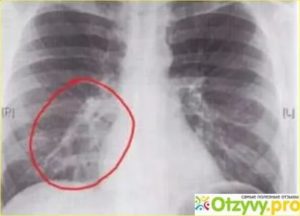

Признаки бронхита на рентгене будут специфическими. Сам воспалительный процесс не определяется, но внимание стоит обращать на тени. Поскольку лучи проникают через стенку и воздушное пространство альвеол, при развитии заболевания будут виднеться кольцевые пятна. Также проявляется и хроническая форма.

Заподозрить бронхит на рентгеновском снимке можно по таким показателям:

- изменяется рисунок легких и сосудов (по виду напоминает разветвление у дерева);

- разрастание соединительной ткани определяется как сгущенные корни;

- в некоторых местах имеются спадания ткани органа.

Бронхит на рентгене выглядит, как чередующиеся зоны низкой и высокой воздушности. Детальному рассмотрению подлежат корни легких, поскольку происходит их деформация.

Именно эти изменения четко определяются на снимке, так же как и чрезмерное разрастание фиброзной ткани. Зная о том, как на рентгене выглядит бронхит, не стоит пытаться самостоятельно сделать расшифровку.